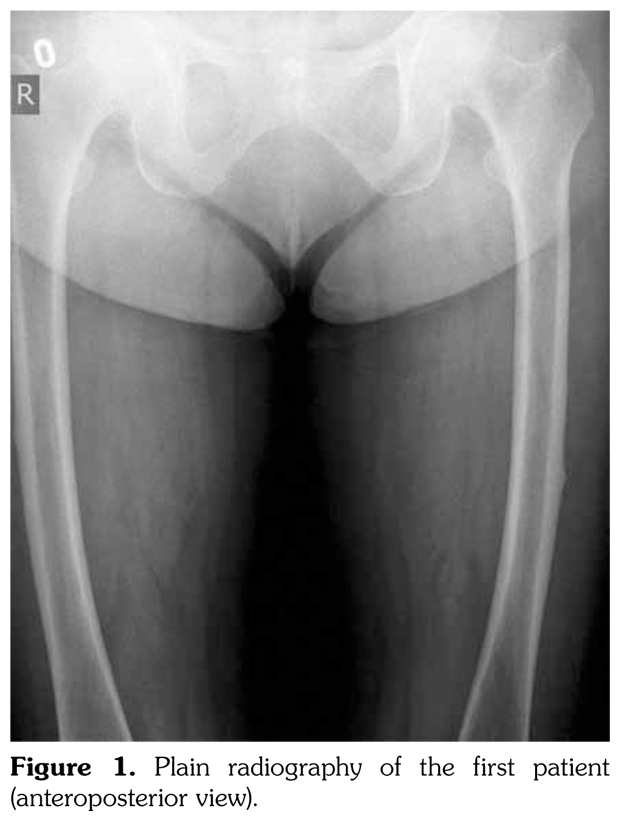

Case 1– A 73-year-old female patient presented with low back, knee, and anterior thigh pain. Pain severity was 8 over 10 point according to visual analog scale. She had difficulty in walking because of pain. She had a history of arthroscopic knee surgery for meniscal pathology in her left knee five years ago. She had chronic low back pain due to L4-5 disc herniation and lumbar spinal stenosis. She had been treated for osteoporosis with alendronate for two years, then with salmon calcitonin for two years and ibandronic acid for a year. Neurological examination was normal. Plain radiographs revealed bilateral lateral cortical thickening in the femur (Figure 1). Magnetic resonance imaging was done to rule out fracture. Bone scintigraphy showed increased uptake in bilateral femoral diaphysis. Routine biochemical tests were normal except increased urinary deoxypyridinoline. Urinary deoxypyridinoline level was 63 nM/mMCre (normal range: 3-7.4 nM/mMCre).

Bone mineral densities and T scores of L2-L4 vertebra and femur neck were 1.088 g/cm(2), -0.9 and 0.761 g/cm(2), -2, respectively. After the radiographical evaluation, bisphosphonate treatment was stopped and bed rest was advised. Walking with crutches and activity restriction for two months were recommended. Analgesics, calcium and vitamin D, and strontium ranelate were prescribed. Physiotherapy including strengthening exercises was planned. The patient was informed about the risk of fracture. It has been two years since the diagnosis. Pain severity decreased and there is no reported fracture.